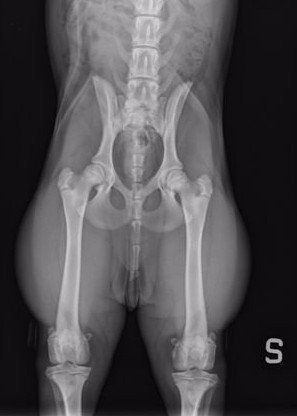

La displasia dell’anca è una malformazione articolare che si sviluppa durante la crescita del cane. Consiste in un errato accoppiamento tra testa del femore e acetabolo, che causa instabilità articolare, dolore e progressiva degenerazione della cartilagine.

Presso la nostra clinica, la prevenzione della displasia delle anche inizia con uno studio radiografico approfondito, effettuato in anestesia o sedazione controllata. L’esame è sicuro e permette di valutare l’articolazione anche nei cuccioli, già a partire dai 3 mesi e mezzo di età.

L’indagine comprende:

- visita clinica ortopedica completa;

- radiografie in più proiezioni (standard, distratta, a rana e DAR);

- valutazione della colonna e, se necessario, anche dei gomiti.

Radiologia digitale e controllo ufficiale FSA

Per garantire la massima precisione diagnostica, la nostra clinica dispone di due apparecchiature radiologiche digitali ad alta risoluzione.

- Una dedicata alla radiologia generale, ideale per lo studio di anche, gomiti e articolazioni.

Le radiografie ufficiali per la classificazione FSA della displasia vengono eseguite secondo i protocolli riconosciuti a livello nazionale, assicurando tracciabilità e validità dei referti.